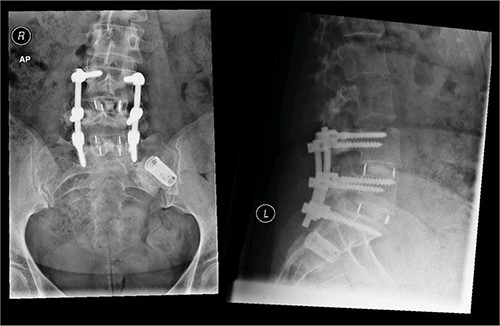

Postoperative X-ray of the pelvis following the second fusion surgery: postoperative X-ray of the pelvis, performed in January 2016 following the second fusion surgery, showing 360° (front and back) fusion of the L4/5 and L5/S1 disc space.